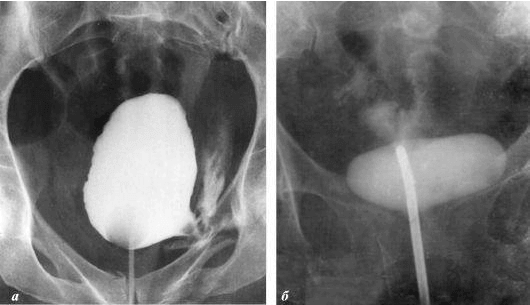

Prostatakrebs bei einem Mann mit 58 Jahren.